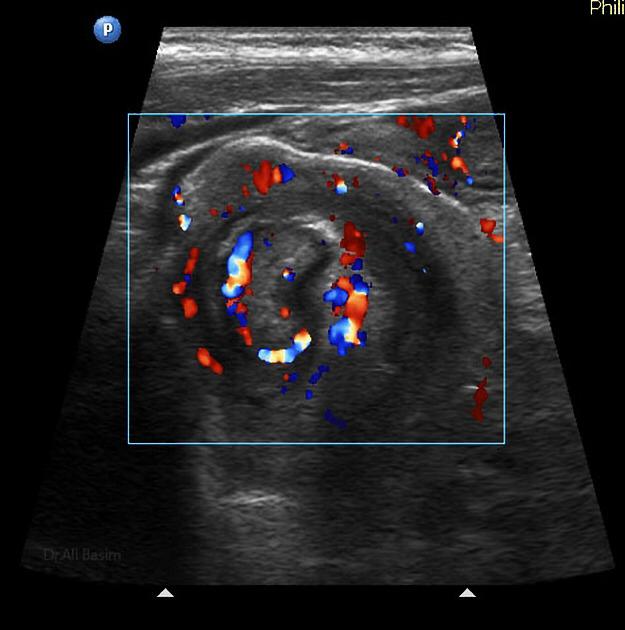

Ultrasonido de Glándula Tiroides

El término nódulo tiroideo se refiere a cualquier crecimiento anormal de las células tiroideas que forman un tumor dentro de la tiroides. Aunque la gran mayoría de los nódulos tiroideos son benignos (no cancerosos), una pequeña proporción de estos nódulos sí...